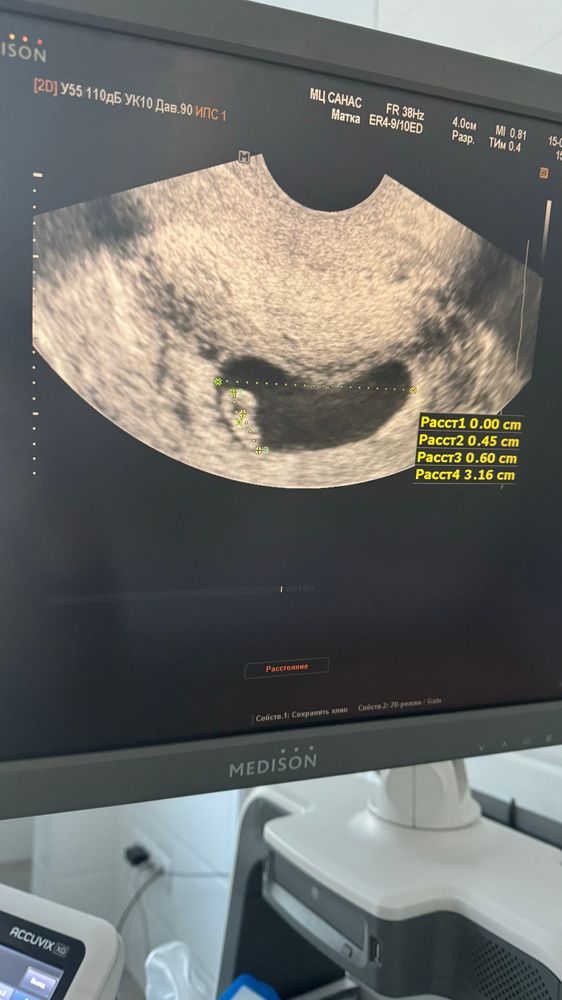

15.01 была на приеме и узи у своего гинеколога ❤️ чсс 138. Первый раз увидели. Ктр 6мм. Муж ходил со мной, умилялся сердечку пульсирующему))